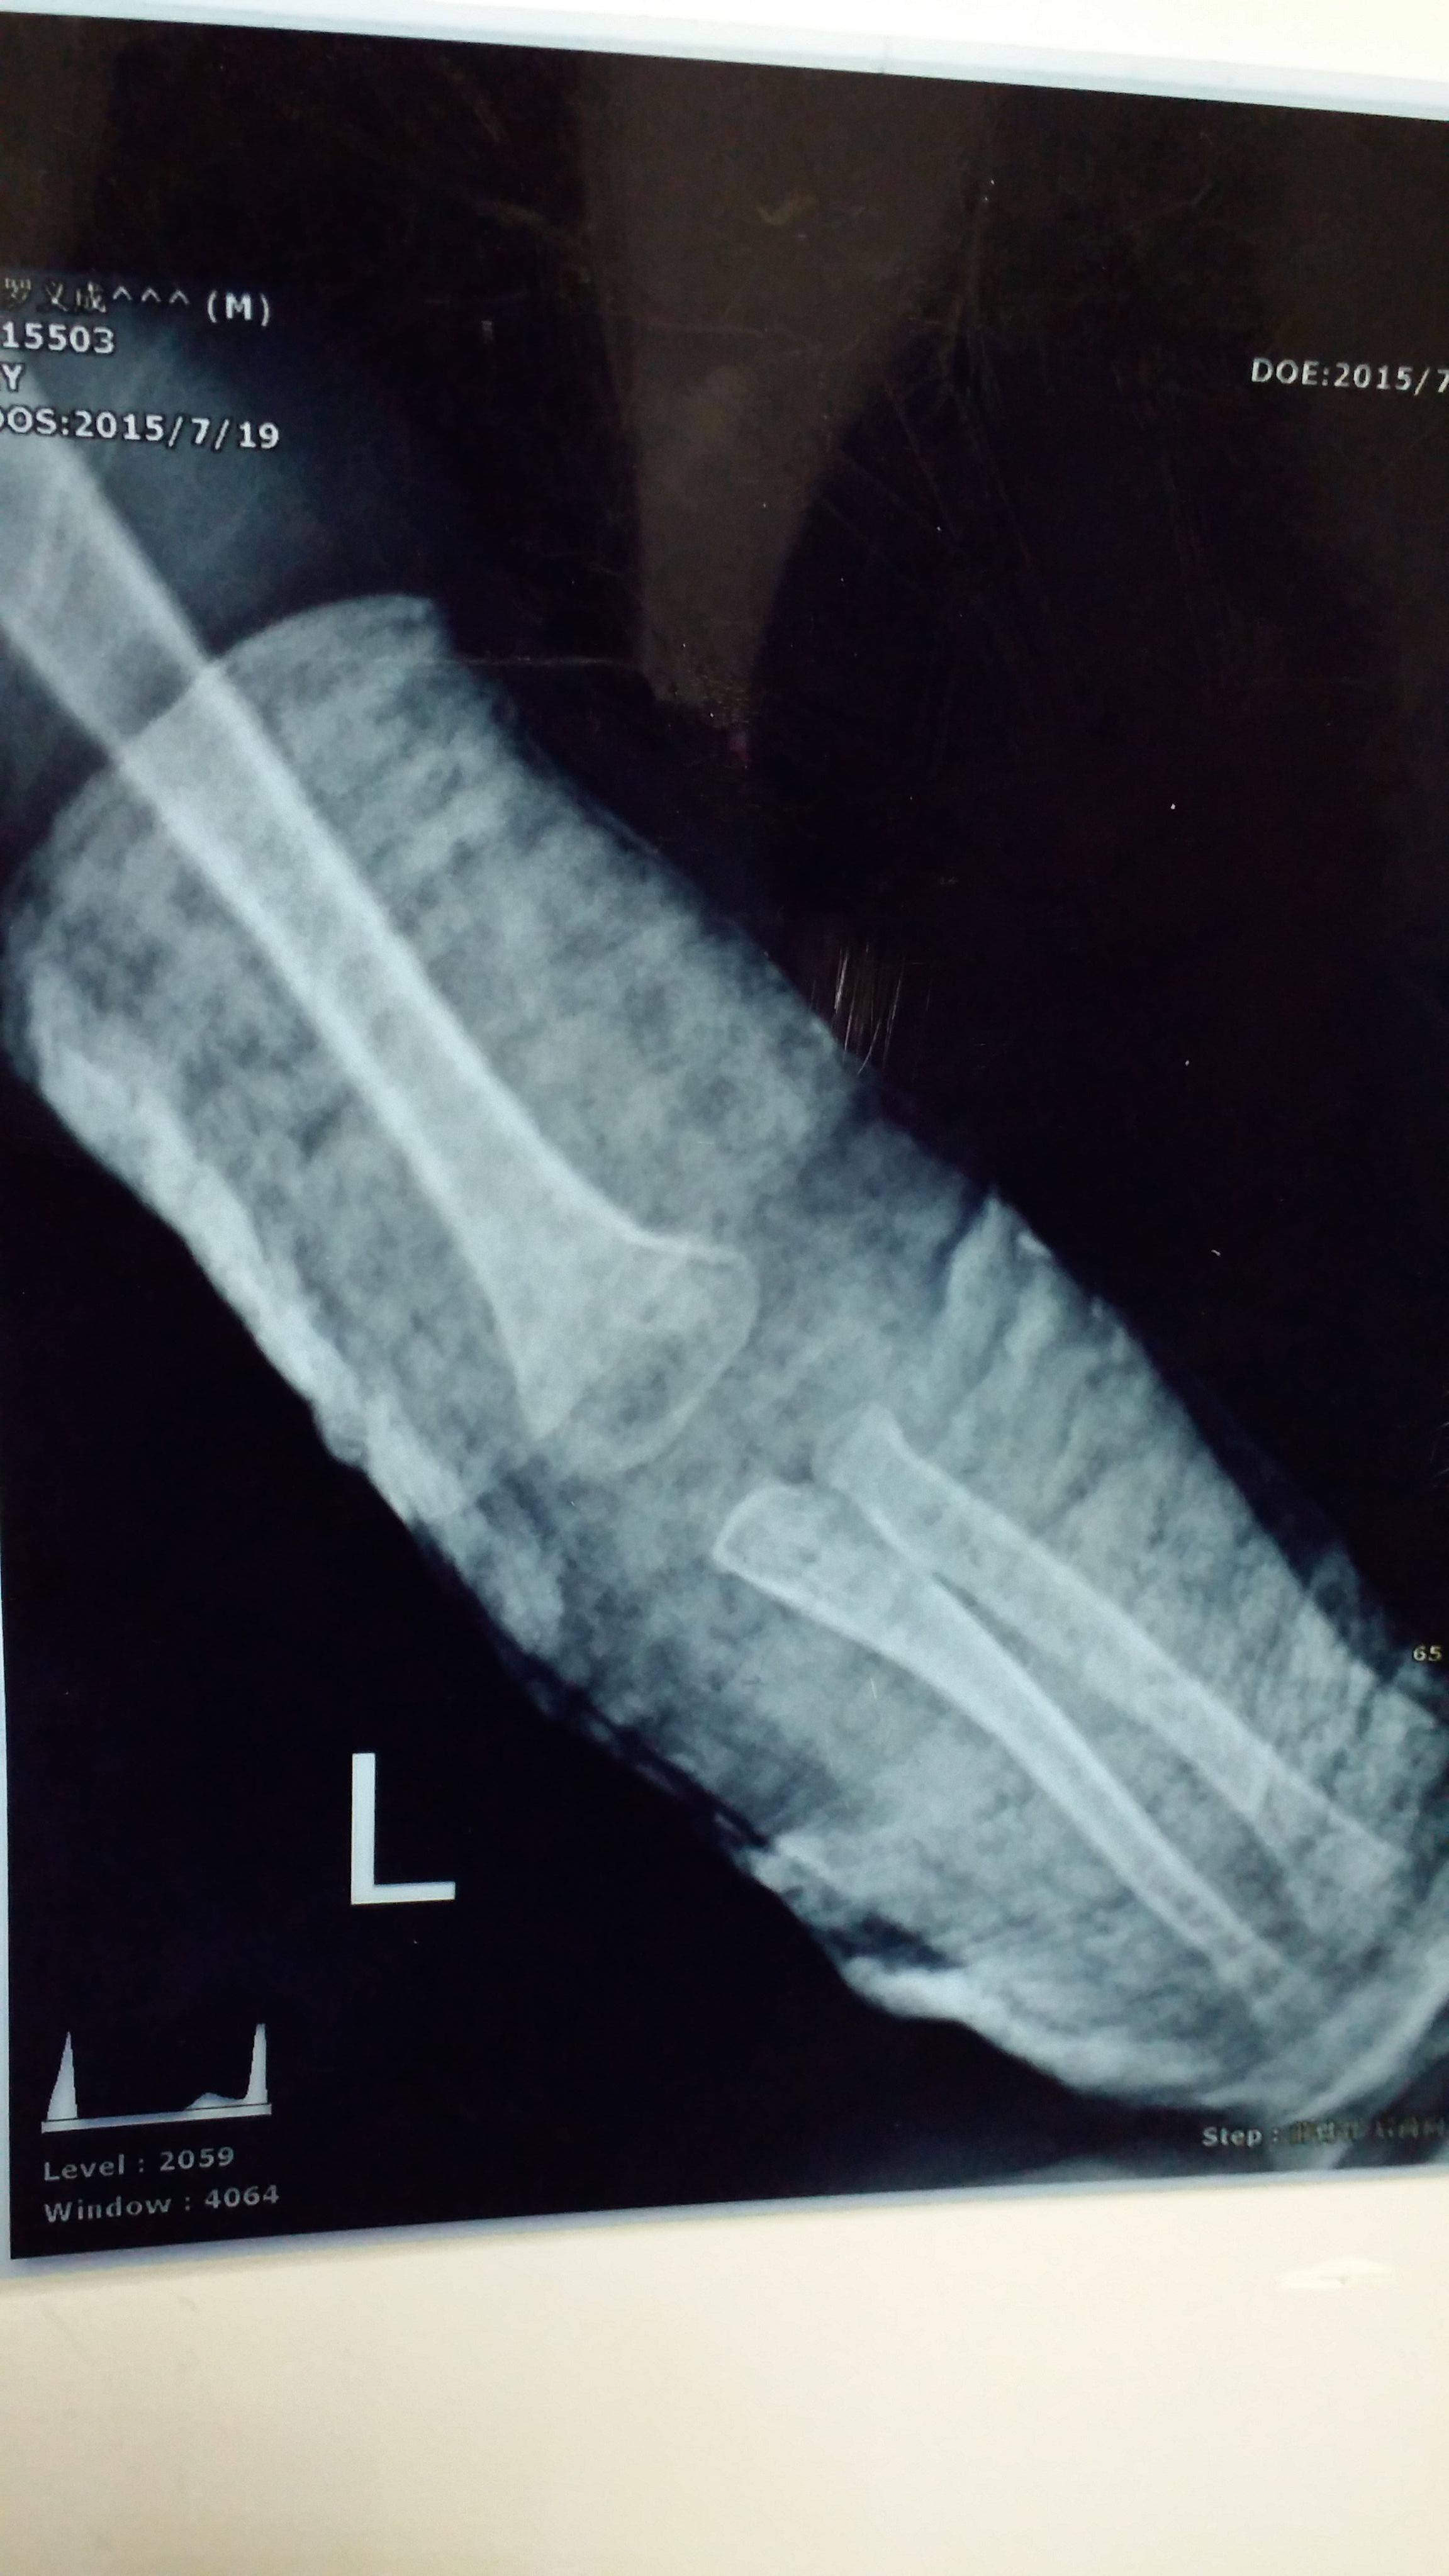

没打石膏是刚摔到拍的 打石膏是今天复查的 请问恢复得好吗?需要打多久石膏?宝宝一岁半 点击展开 匿名用户 2015-07-19 22:49 为您推荐: 其他回答 你好,根据你所描述的情况及提供的片子来看,尺桡骨脱位,行复位后外固定即可。石膏固定1个月左右。 sΰ 2015-07-19 23:23 相关问题 四个月宝宝,半个月复查,医生说再过6天恢复可以就能去石膏了 孩子左肱骨髁上骨折一周后的复查片子,麻烦医生帮我看看恢复的怎么样呢?还有医生为什么把石膏割了一个大 八岁孩子今天上体育课,被其他孩子推了以后,到医院检查,右肱骨髁上骨折,打完石膏回到家,现在不知道要